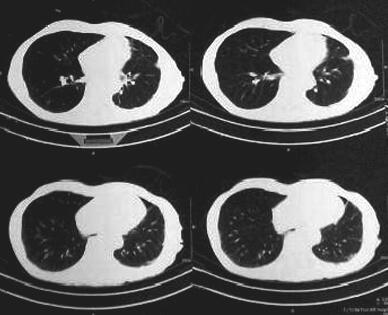

在对症支持治疗基础上,连接负压瓶给予持续负压引流,负压控制在0.2~0.5kPa之间负压引流时左肺可复张,但持续有气泡溢出,夹闭引流管后肺压缩反复出现。入院后第2日引流瓶内气泡生成减少,行胸部CT示:左侧少量气胸、左侧胸膜肥厚、粘连(图3)考虑肺复张。于入院后第24、28、31、33、35日胸膜腔内注射白介素-2 200万单位,注射后闭管6小时再开放引流。入院第35日夹闭引流管24小时后气胸无反复,胸膜腔引流量小于100ml,于入院后第36日行胸部CT示:左侧胸腔积液,左侧胸膜局部增厚、粘连,(图4)考虑左肺脏层胸膜已愈合。出院后随访3个月,未再发生气胸及胸腔积液,其后患者失访。

图3 胸部CT(引流术后第21天)

左侧少量气胸、左侧胸膜肥厚、粘连

图4 胸部CT(引流术后第35天)

左侧胸腔少量积液,左侧胸膜局部增厚、粘连